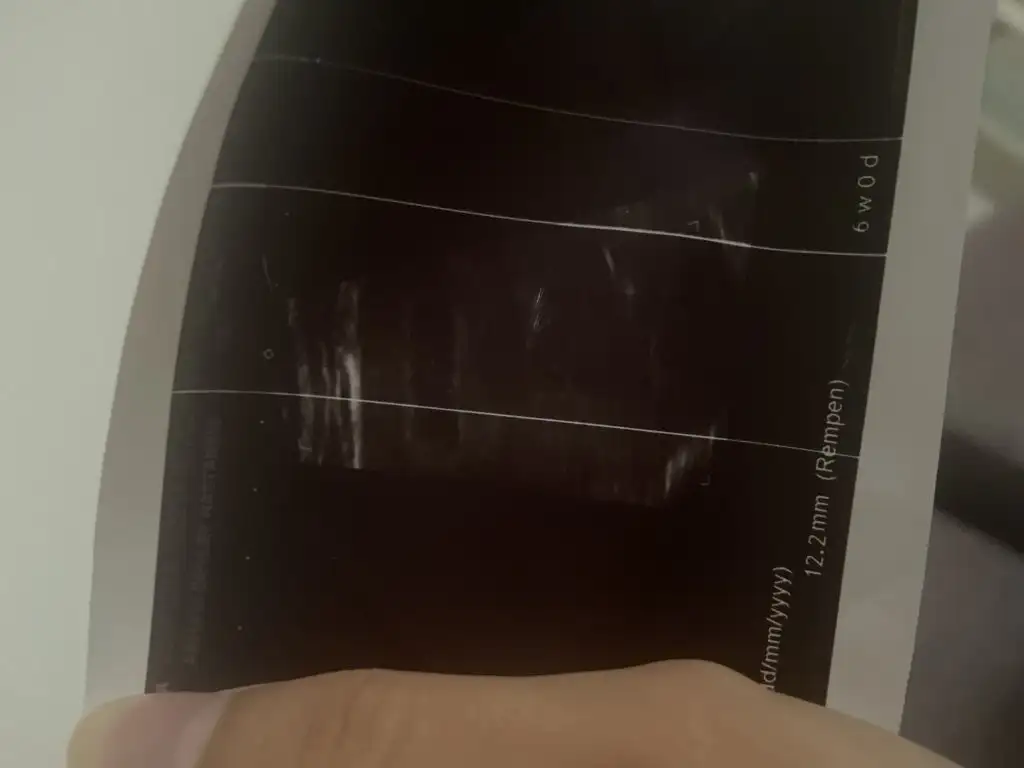

5 hafta 1 günlük hamileyim gebelik kesesi resimdeki gibi biraz karanlık umarım yorumlarsınız kese çapı 12,2 mm normal mi acaba birde doktor bebeğin görünüp görünmemesi hakkında birşey demedi normal dedi sadece ama sizde bilgi verirseniz çok sevinirim

• image.webp

9,4 KB · Görüntüleme: 107